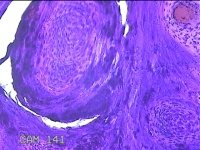

右侧中指皮下结节

性别

男

年龄

41岁

临床诊断

皮下结节

一般病史

发现右侧中指皮下结节3年余,无明显疼痛及不适。

标本名称

大体所见

灰白暗红色结节0.7x0.3x0.2cm一个,表面糜烂。